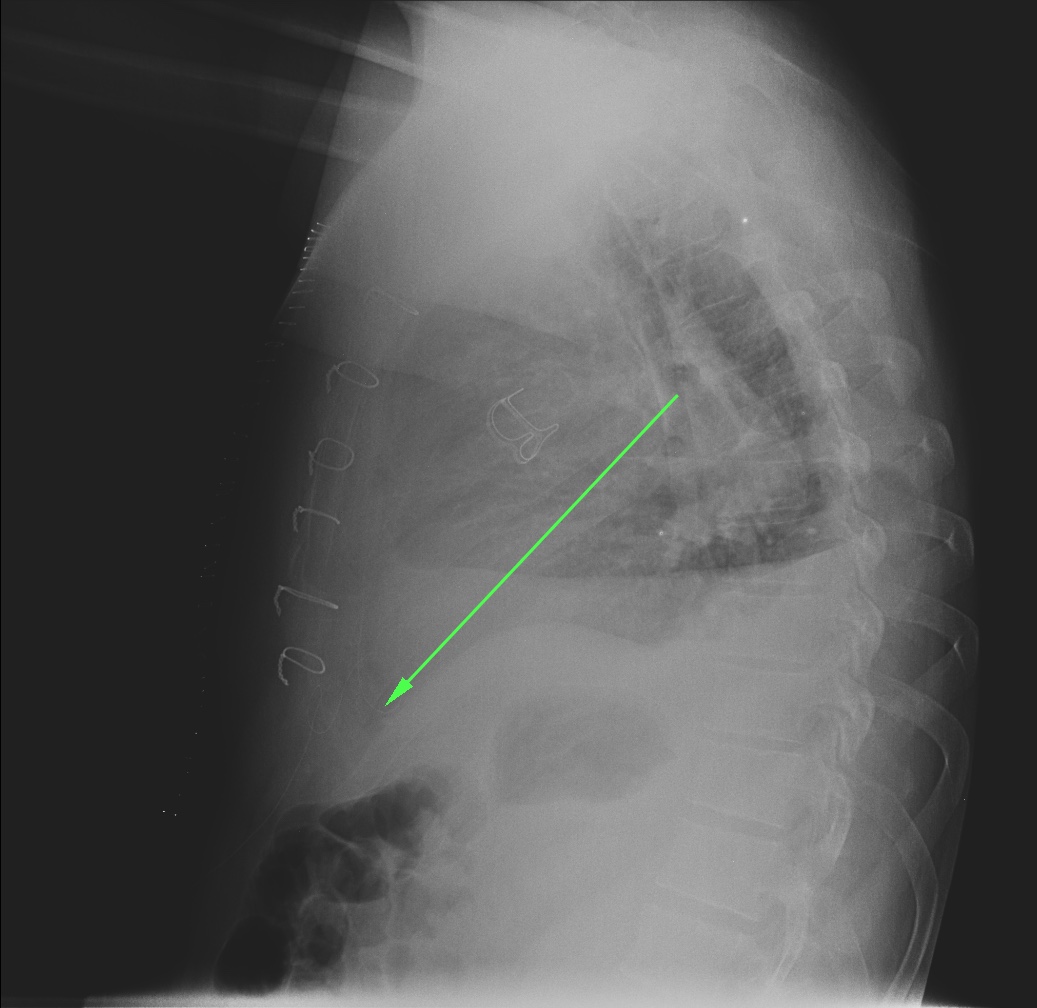

CASO: Operada de cáncer de mama izquierda en revisión.

Hallazgos:

- Prótesis mamaria izquierda (obsevar el aumento de densidad homogéneo y de bordes bien definidos en la placa PA y lateral)

- Parénquimas pulmonares y silueta cardiomediastínica sin alteraciones significativas.